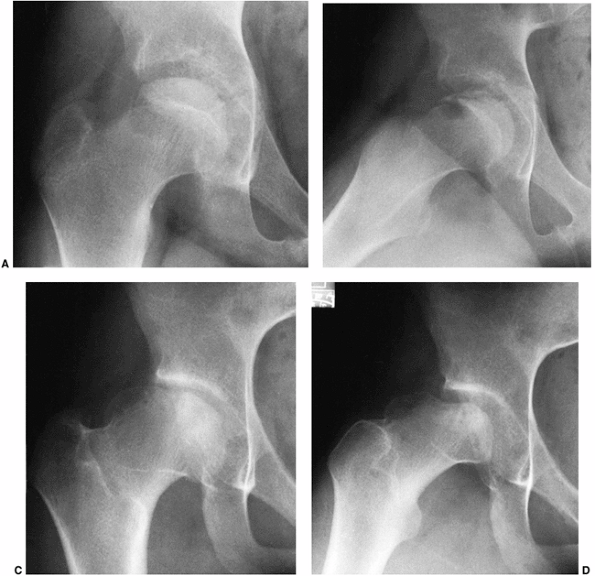

reported a 33-year follow-up of 35 patients. Twenty-eight of the 35

spherical femoral heads, as rated by the Mose Sphericity Scale (204) (Fig. 25.16). Forty-three percent of the patients had poor Mose ratings; however, of these patients, 76% had good clinical results.

begins to deteriorate. In another study of the Iowa group of patients

at 48-year follow-up, McAndrew and Weinstein (203)

reported that only 40% of patients maintained an Iowa Hip Rating of

better than 80 points. Forty percent of the patients had undergone

arthroplasty, and an additional 10% had disabling osteoarthritis

symptoms but had not yet undergone arthroplasty (Fig. 25.17).

Figure 25.17

This patient had disease onset at 8 years and 3 months of age. At 46 years of age (38-year follow-up), the Iowa Hip Rating was 88 points (A). At 58 years of age (50-year follow-up), there was a loss of 21 points on the Iowa Hip Rating, to 67 (B). At 60 years of age, just before arthroplasty, the Iowa Hip Rating was 60 points (C). (From Weinstein SL. Legg-Calvé-Perthes’ disease: results of long-term follow-up. In: Fitzgerald RH Jr, ed. The Hip: Proceedings of the Thirteenth Open Scientific Meeting of the Hip Society. St. Louis, MO: Mosby, 1985:28.) |